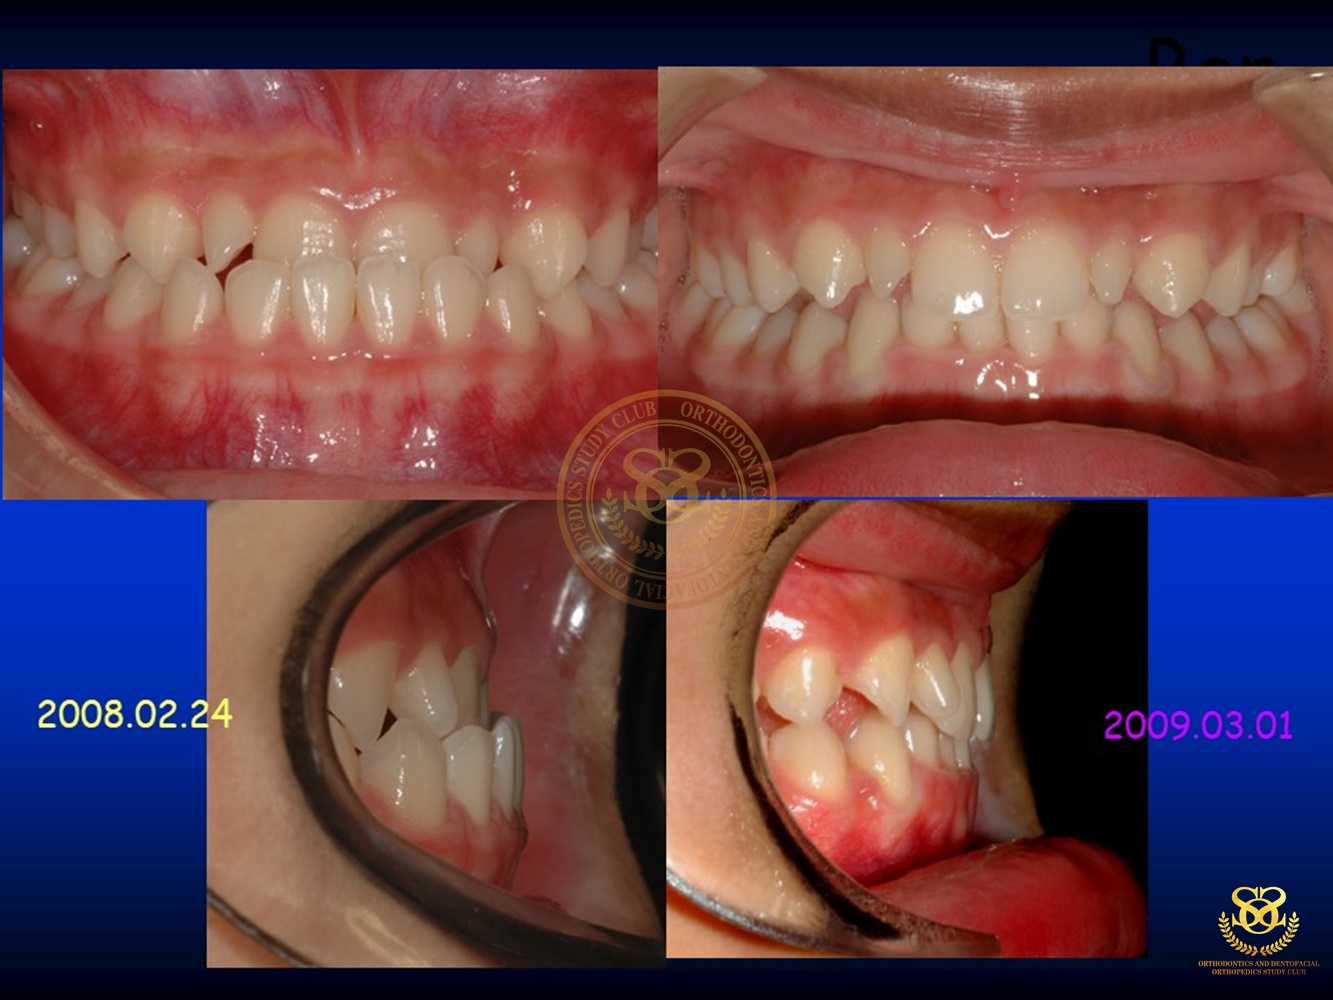

เคสตัวอย่าง Ben.Early Class III Tx.v.2018.CURRENT 2019-10-181168 views0 By Dr.Schwan Somsiri Share Share Share